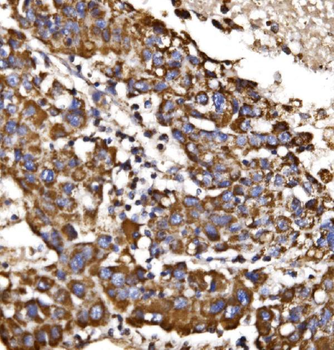

- PPM1D Rabbit Polyclonal Antibody [orb704535]Featured

IF, IHC-Fr, IHC-P

Human, Mouse, Rat

Rabbit

Polyclonal

Unconjugated

100 μl, 50 μl, 200 μl - HSC70 Mouse Monoclonal Antibody [orb704174]Featured